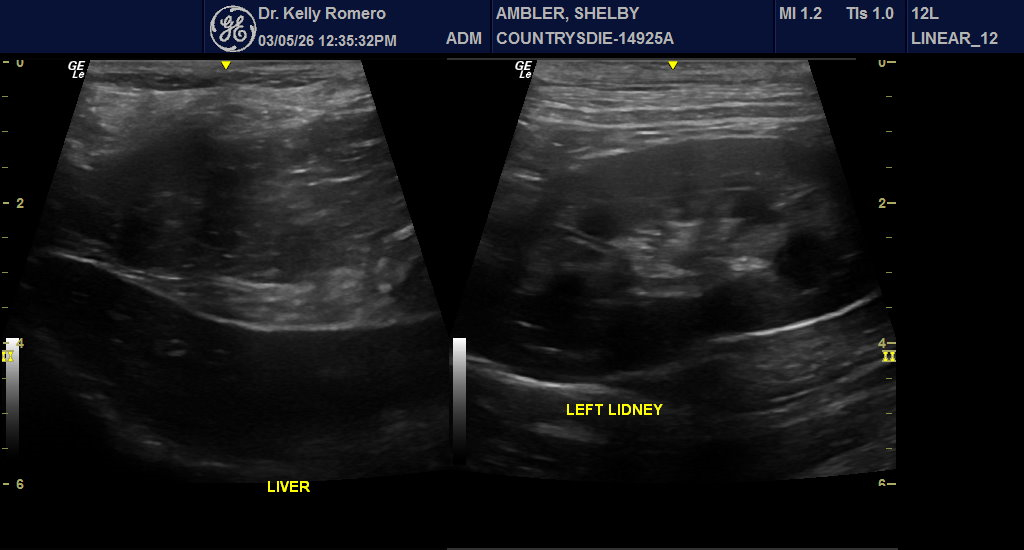

7 year 9 month old FS Chow with lethargy, vomiting and intermittently dribbling blood tinged urine. CBC WNL. Chem – ALT 773, ALP 389, GGT 31, T bili 0.5. Looks like choleliths in biliary tree, but focal region. No reported fever. Started Ursodiol, Denamarin, and antibiotics for cholangiohepatitis (Clavamox and metrondizadole). Urinary bladder looked unremarkable. There was a hyperechoic nodule in the otherwise normal left adrenal gland.

Hi Eric, thank you for taking a look! When I go back through, I can see where some of these hyperechoic choleliths could actually be in the gall bladder instead of outside of it – is there an artifactual phenomenon that causes them to look more like they are outside of the lumen at least in some views or do you think it is a combination of choleliths in the GB and the nearby tree?

I tried multiple positions, including SDEP 11, 12 and 13 and really struggled to image the cystic duct into the CBD. Tips?

Do you think medical treatment is an option in this case while monitoring LE (ursodiol, antibiotics) or best to refer for surgery? CBC looks empty to me, but distended – did I miss a stone in there?